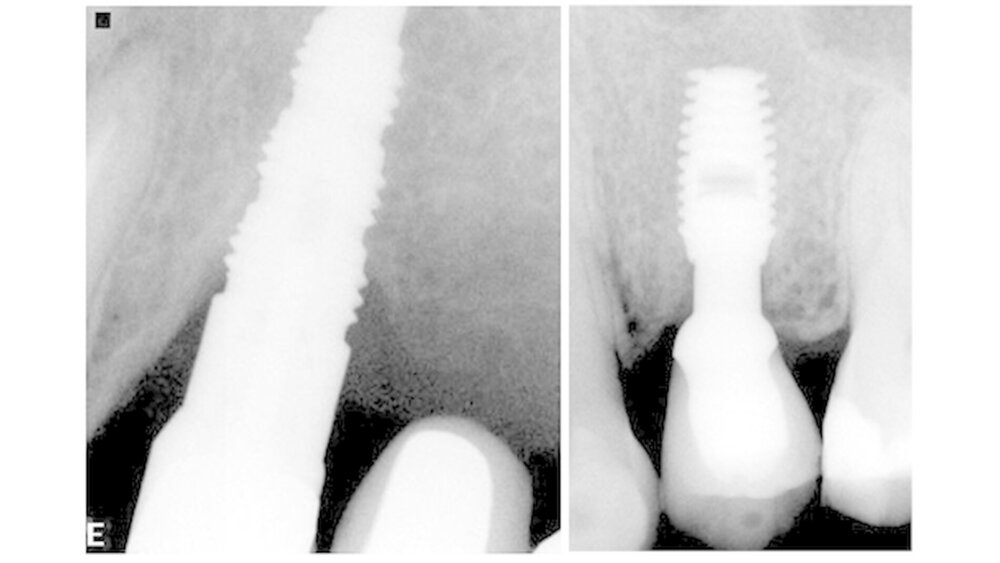

Aus technischer Sicht steht der Knochenschwund mit dem Design des Implantats in engem Zusammenhang. Demnach tritt beim raketenförmigen Design mit unverblockten Kurzimplantaten ein geringerer Knochenschwund auf als bei längeren verblockten Zahnimplantaten. In toto sei der Knochenschwund um das Kieferknochenniveau eines Implantats aber multidisziplinär, was seine Ursachen angeht.

Marincola und Kollegen schlussfolgern, dass bei Einsatz des raketenförmigen Designs - im Vergleich zum vasenförmigen und zum zylindrischen - aufgrund des höheren Knochenanteils um das krestale Modul wahrscheinlich weniger Knochenschwund auftritt. Diese Designform könne eine homogene Verteilung der Aufbisskräfte am Hals des Implantats und am Kieferkamm erreichen. Die reduzierte Präsenz einer Titanoberfläche ermögliche es, so das Fazit der Arbeitsgruppe, diese Implantatgeometrien sehr nah aneinander zu platzieren.